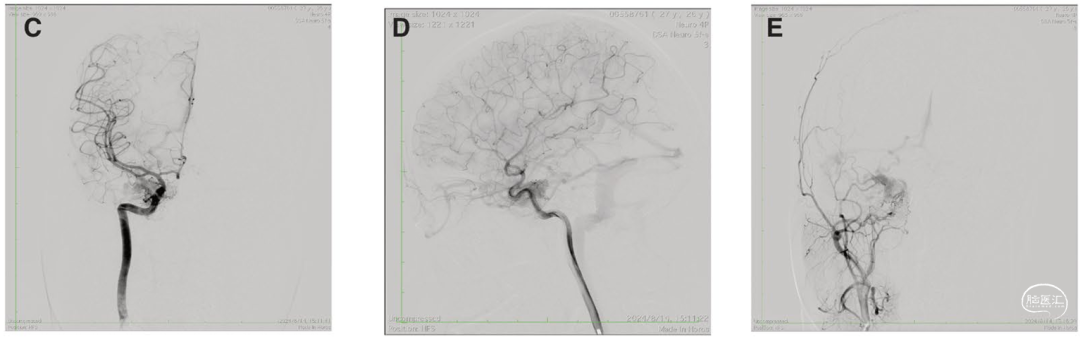

本研究报道了一例27岁女性海绵窦区硬脑膜动静脉瘘(CS-DAVF,Barrow D型)患者的诊疗经过。该患者因轻微头部外伤后出现右侧搏动性突眼及搏动性耳鸣,此前在外院曾尝试两次常规血管内栓塞治疗,均因无法开通岩下窦、面静脉等通路而失败。患者随后转诊至华山医院,经数字减影血管造影(DSA)检查明确诊断:病变血供主要来源于右侧颈内动脉脑膜垂体干、右侧咽升动脉以及左侧颈内动脉脑膜垂体干,静脉引流则以眼下静脉为主。

手术在复合手术室内完成。介入团队经股动脉穿刺,留置造影导管用于术中实时评估;神经外科团队则经鼻腔入路,在内镜下显露并切开海绵窦内侧壁硬膜。随后,在双重视觉引导下,将工作鞘管精准置入海绵窦腔内,建立起直达瘘口的稳定通道。

栓塞采用了分阶段栓塞的策略:首先置入弹簧圈以减缓血流,随后注入onyx-18液体栓塞剂,完整填充瘘腔及引流静脉,形成致密铸型,最终实现异常血流的永久阻断。

术后,患者原有的搏动性耳鸣症状完全消失。复查影像显示瘘口已完全闭塞。患者术后仅出现一过性复视,在一个月内基本恢复。三个月后的血管造影证实,海绵窦区异常血管团完全消失,达到了解剖学上的治愈。